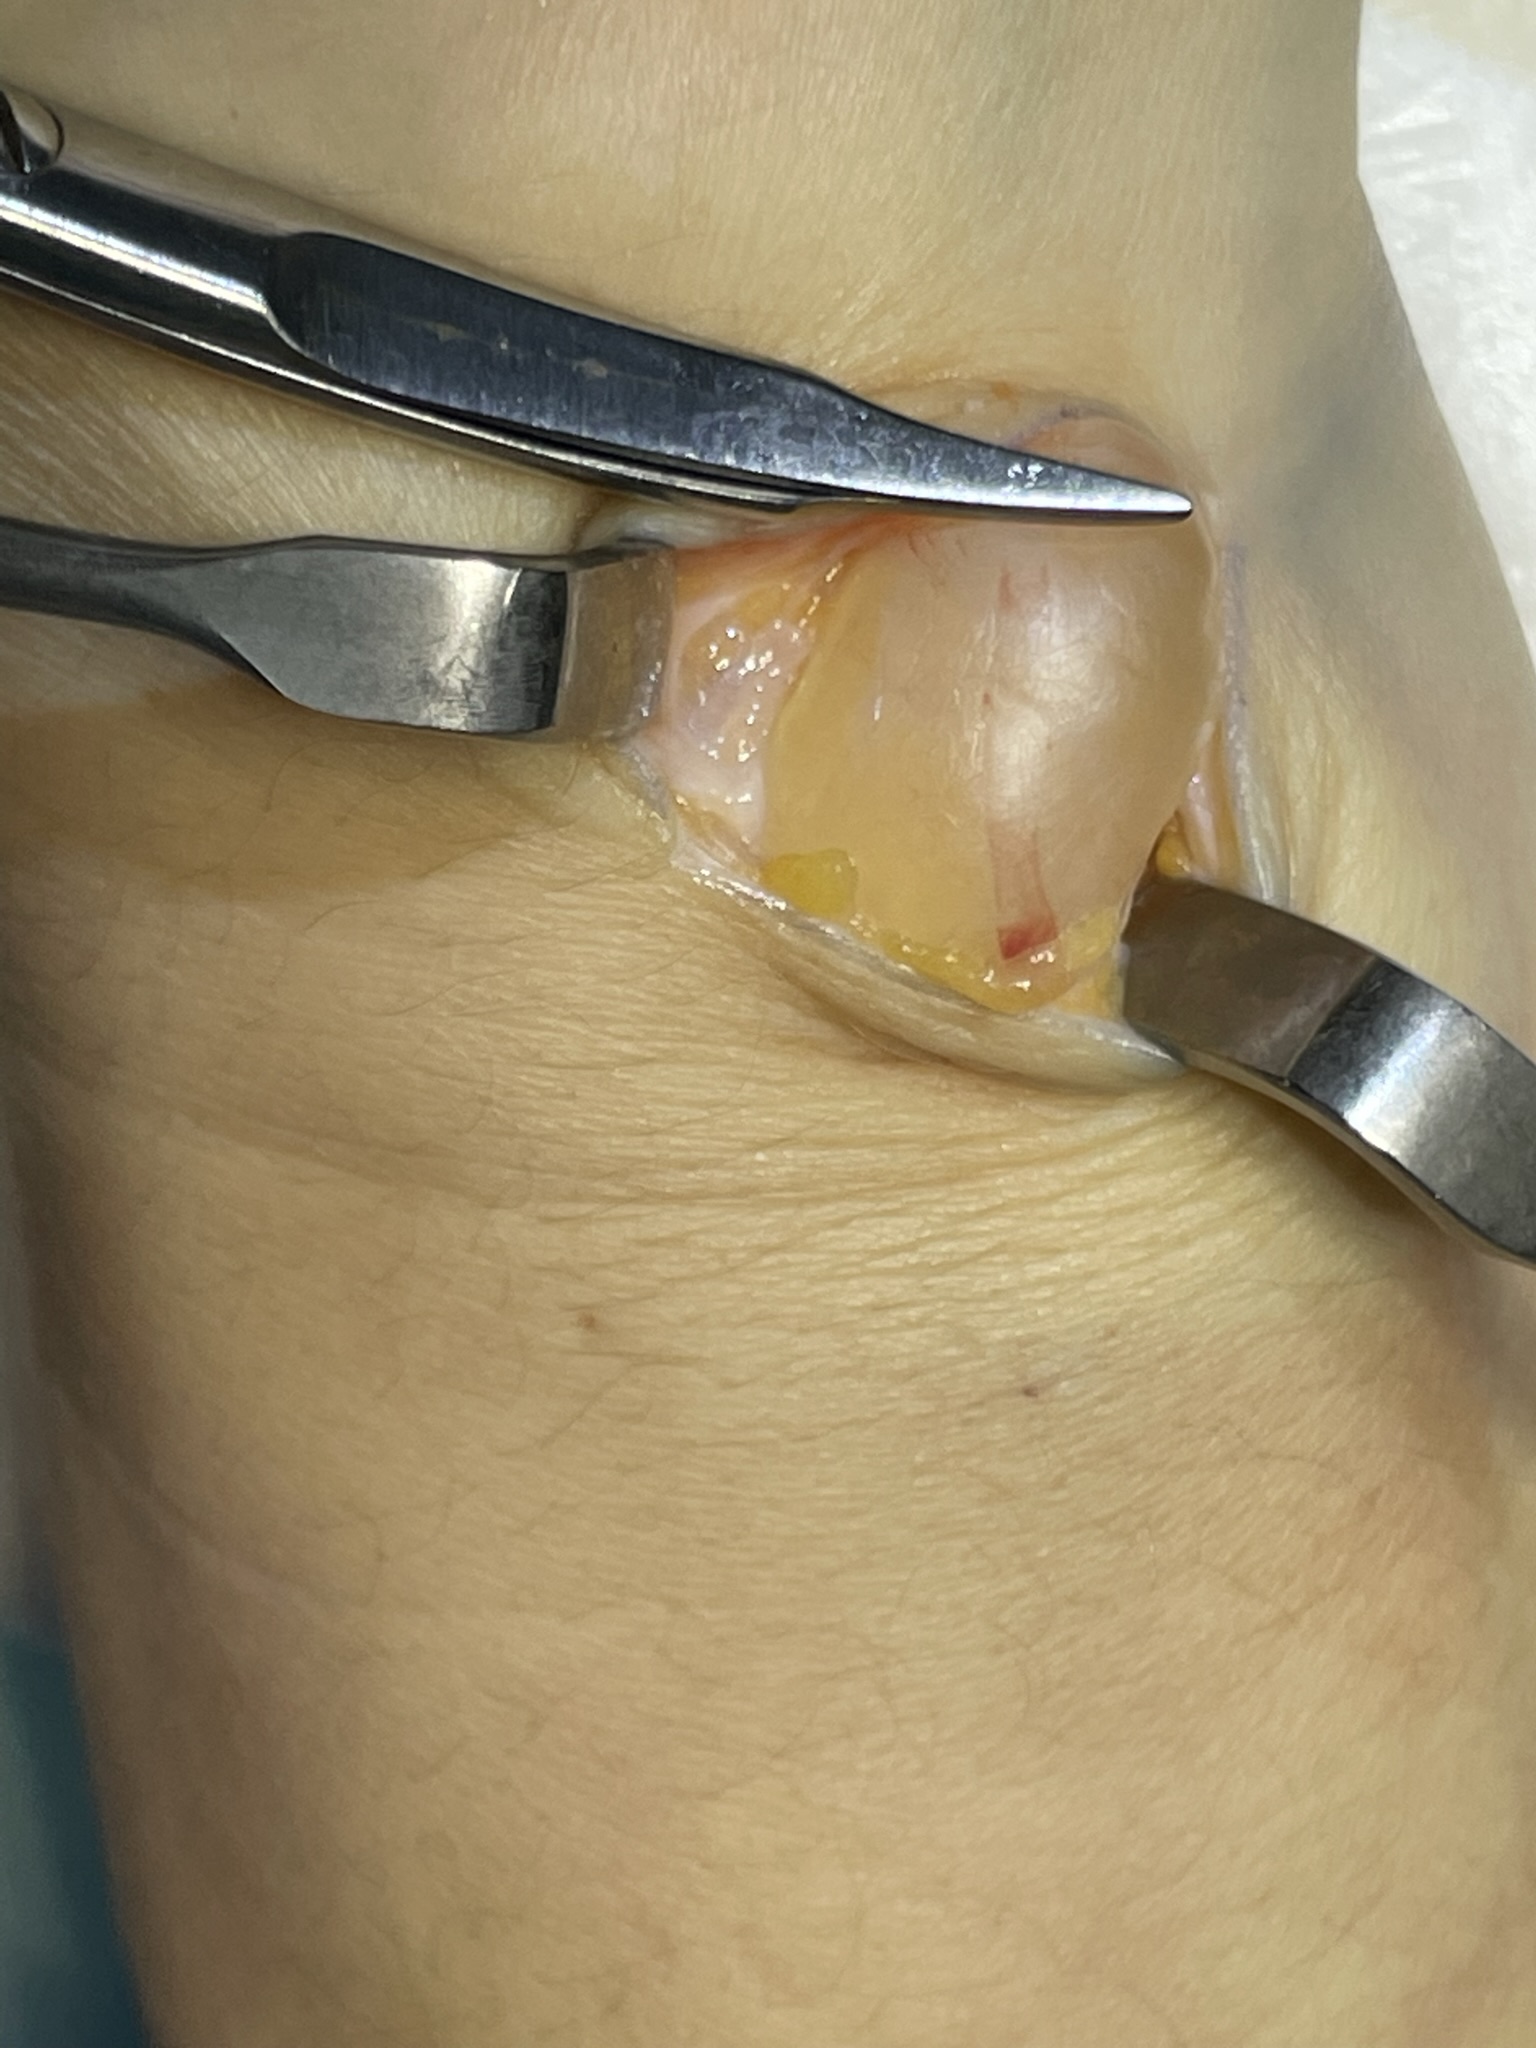

Клинический случай: тыльная гигрома запястья

Пациент с тыльной гигромой, подтверждённой на УЗИ. Выполнено хирургическое лечение, документированы этапы контроля и результаты.